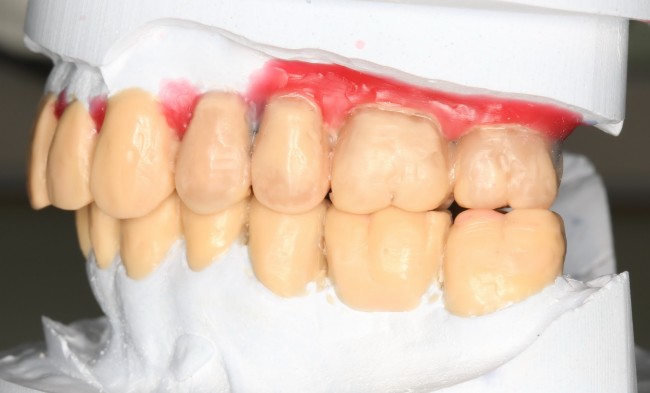

Во время диагностики мы нередко делаем слепки и диагностические модели, устраиваем консилиумы с привлечением всех необходимых специалистов. В наших клиниках нет врачей-универсалов, поскольку каждый занимается только своим делом и своей специальностью, достигая в ней определенных высот. И, конечно же, мои ортопеды или ортодонты разбираются в протезировании или патологии прикуса лучше меня — так давайте я позову их и они вам все расскажут! Две думающие головы всегда лучше, чем одна, верно?

По диагностическим моделям и функциональной диагностике можно изготовить восковую модель будущей протетической конструкции. Нередко по ней определяется тактика предстоящего лечения, изготавливаются хирургические шаблоны, временные протезы и т. д. Необходимость создания восковой модели определяет врач-стоматолог-ортопед совместно с хирургом.